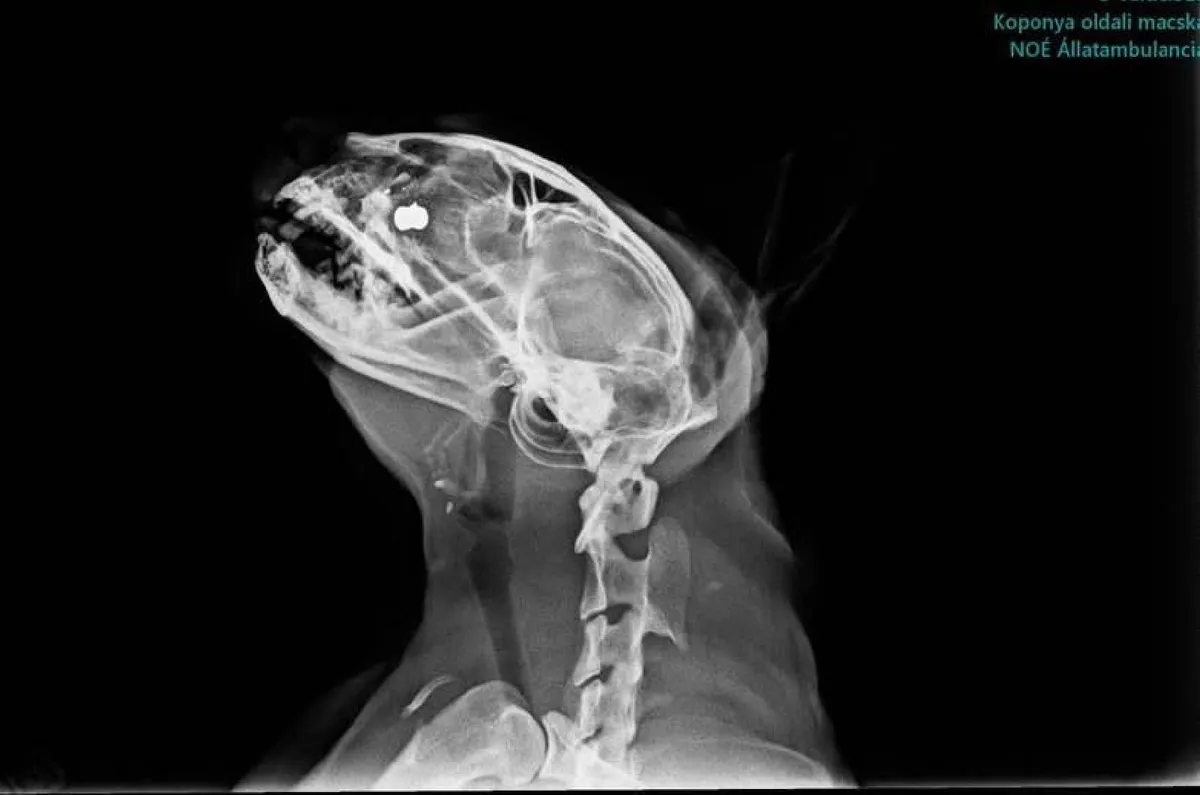

A Vas megyei hírportál számolt be róla március 23-án, hogy a szombathelyi Parkerdőben fejbe lőttek egy macskát. Az állat súlyos sérüléseket szenvedett, ugyanis a golyó megállt a szeme és az agya között.

A Mogyoró nevű cicánál elsőre úgy tűnt, hogy nem lehet műtét utján kiszedni a lövedéket. Ráadásul el is fertőzödött a sérülése, így Alexandra, az állat gazdája már a kiskedvence halálára készült.

A macskáról készült röntgenképet megosztotta közösségi oldalán, amelyen látható, hogy milyen mélyre fúródott a golyó.

A bonyolult, kétórás műtét sikeréről kedden számolt be a hírportál, amelyen megerősítették, hogy csodával határos módon túlélte Mogyoró, ám a felépülése alatt még akadhatnak komplikációk.